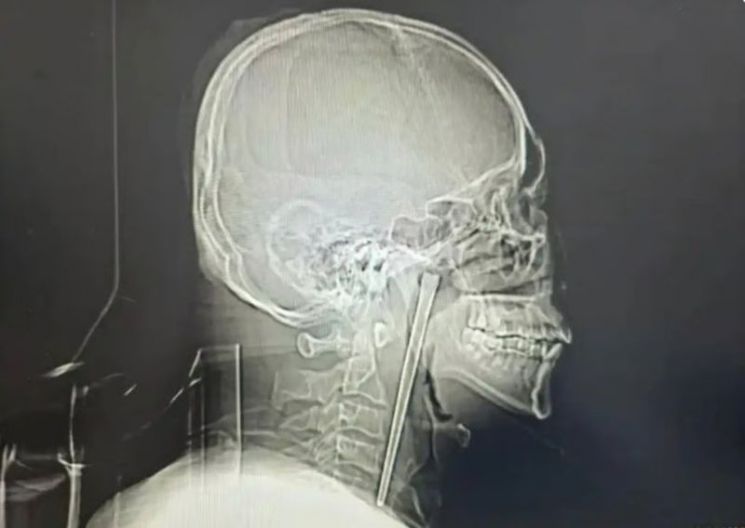

20일(현지시간) 홍콩 매체 사우스차이나모닝포스트(SCMP)는 이달 초 수술을 받은 중국 남성 A씨의 사연을 전했다. A씨는 목에 12㎝ 젓가락이 박힌 상태로 8년을 버티다가 최근 수술을 받아 제거했다.

남성의 목에 박힌 금속 젓가락. 바이두 캡처

정밀 검사 결과 A씨가 8년 전 삼킨 금속 젓가락은 입천장 뒤에 위치한 목 안쪽 연구개 부위에 박혀 있었다. 다행히 목 주변 점막은 손상되지 않았고, 성대도 정상적으로 기능했다.